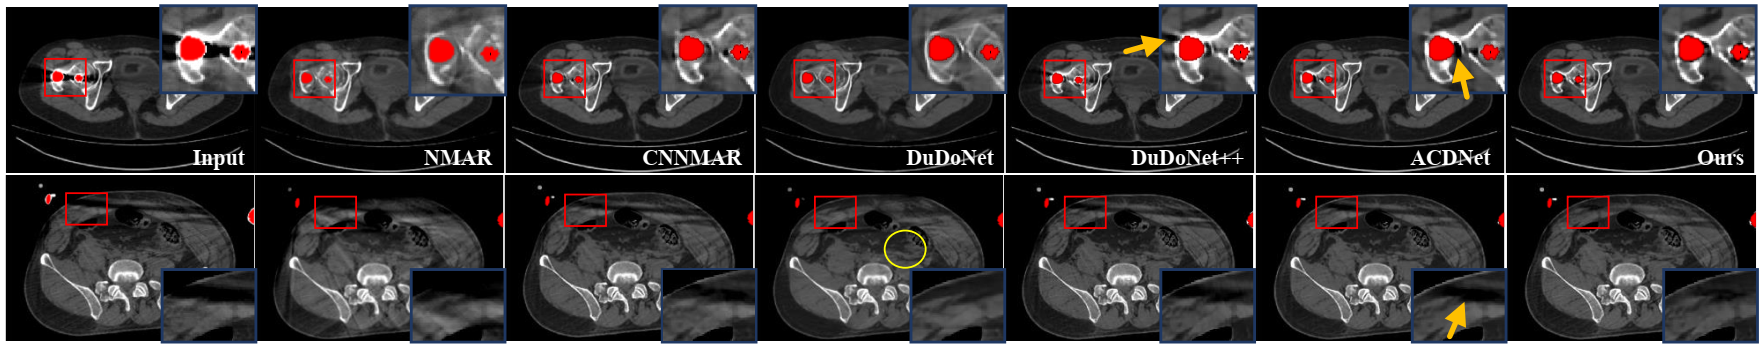

本方法在两个数据集(仿真金属伪影数据集Deeplesion、临床数据集CLINIC-metal)开展了实验。相比于其他金属伪影去除方法,本方法极大提高了金属伪影去除效果。部分实验结果如图5所示。

图5:与几种金属伪影去除方法的临床数据集对比结果。